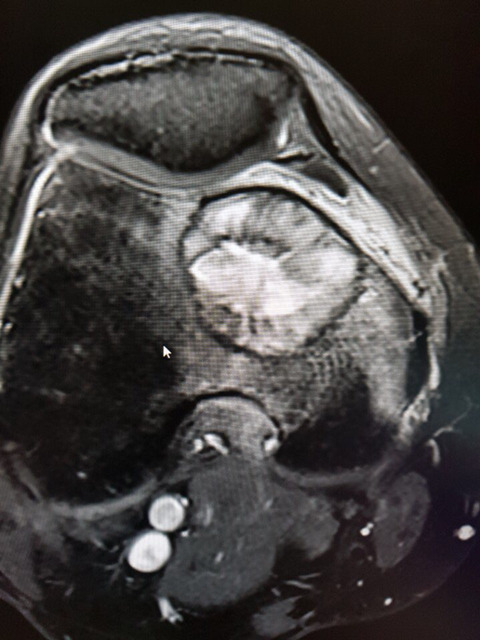

무릎 거대세포종

6월부터 통증있다가 8월말 mri 찍고 삼성의료원 방문하여 조직검사 후에 9.13 거대세포종 판정 받았습니다.

수술은 10.5 예정이고, 교수님께서 골 소파술 이후 골시멘트로 채울 계획이고, 관절은 안건드린다고 하셨습니다.

크기는 지름 3.5cm

• 작성자소중한분 작성자 본인 여부 작성자 | 작성시간 18.10.09 댓글 첨부 이미지 이미지 확대